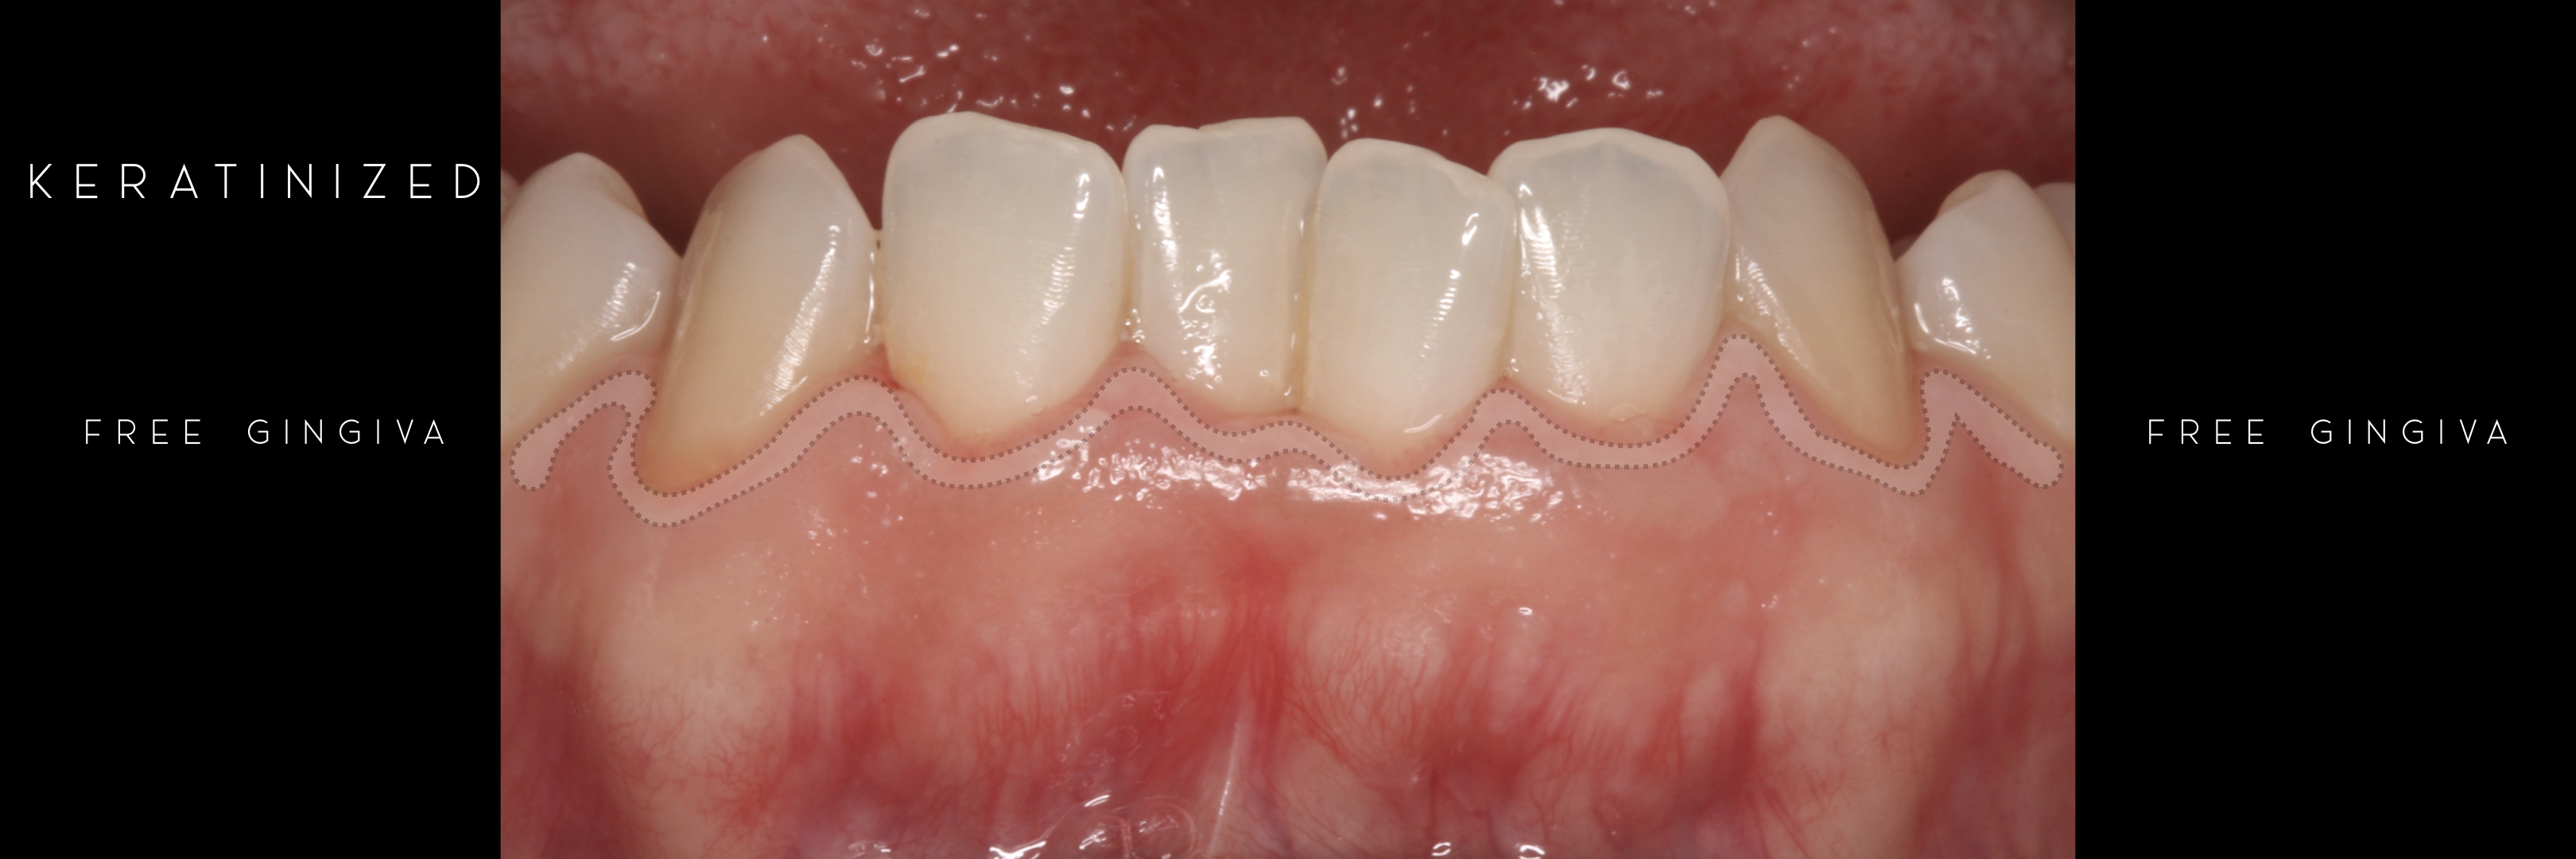

KERATINIZED gingiva includes

the free gingiva

(marginal gingiva & papillae)

and the attached gingiva extending from the gingival mar­gin to the mucogingival junction.

Generally we tend to forget about these 2 parameters, free and the attached gingiva are both essential parts of the keratinized gingiva.

This meaning that keratinized (load bearing capacity) is a mechanical characteristic that makes up for attached gingiva, providing it's immobility,  but also is of such importance as the thickness it provides around whatever perforates the epithelium, be it implants or teeth, being also keratinized (having load bearing capacity) at this location.

However free marginal gingiva is different in characteristics on its outer and inner surfaces: outer surface is keratinized;

inner surface is

non-keratinized, constituting part of the gingival sulcus.